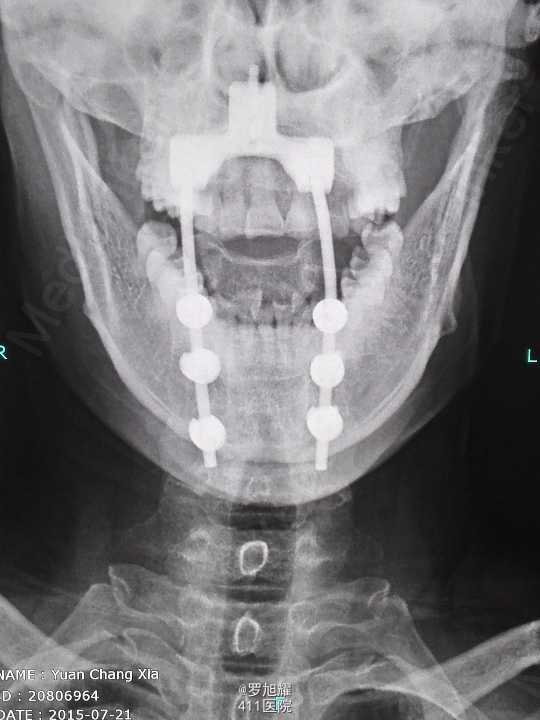

诊断为:颈椎先天畸形、颈2/3椎间盘突出伴不全瘫。 因寰枢关节退变,颈椎活动已部分受限,而且枢椎椎板棘突缺如,稳定性差,决定后路减压枕颈融合。

因寰枢关节退变,颈椎活动已部分受限,而且枢椎椎板棘突缺如,稳定性差,枕颈融合虽然造成颈部活动受限,但是稳定性好,避免脊髓再次损伤。本例手术后半月上肢麻木明显改善,躯干和下肢麻木尚待恢复。